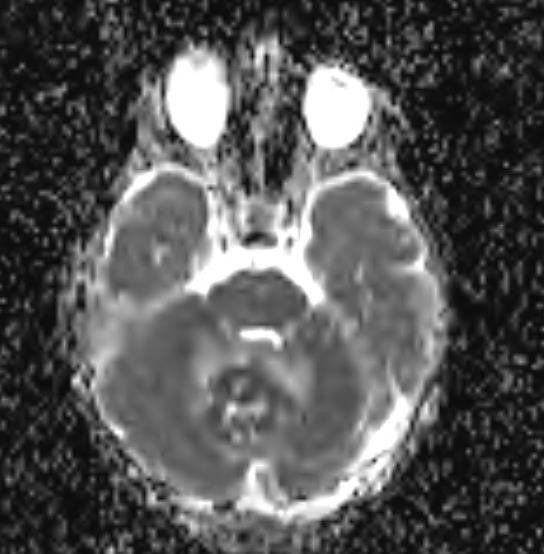

- DWI / ADC sinal DWI alto ("difusão restrita") valores de ADC baixos (cerebelo mais baixo do que o normal, por exemplo, ~ 550 x 10-6 mm2 / s)

A ressonância magnética é capaz de delinear o quarto ventrículo e o espaço subaracnóideo em um grau muito maior do que a TC. Embora os meduloblastomas se projetem para o quarto ventrículo, ao contrário dos ependimomas, eles geralmente não se estendem para as cisternas basais

Como a disseminação do LCR é comum na apresentação, a imagem com contraste de todo o neuroeixo é recomendada para identificar as metástases em gotas e a disseminação leptomeníngea. Embora rara, há relatos de disseminação extraneural.